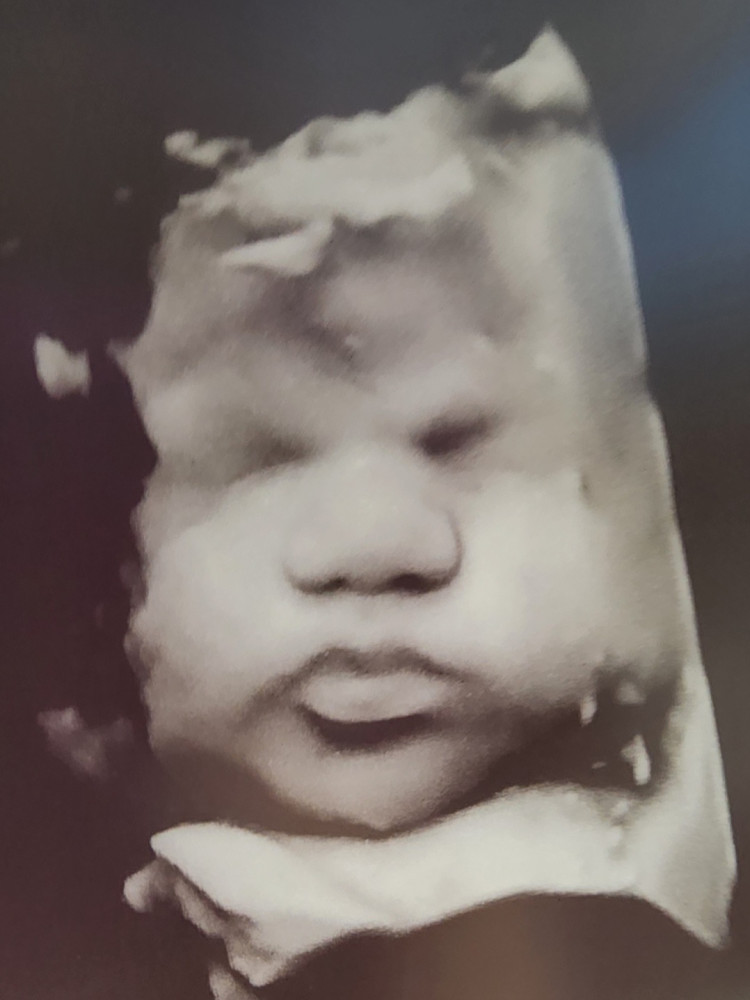

Our sweet baby Adalynne Lee, due September 2, 2025 was diagnosed with 3 congenital heart defects in early April. This month has been heavy for us for many reasons, but we are thankful our little girl is fighting through ❤️ Delivering her looks quite different for us, as we are being placed in the care of St. Vincent, and she will be immediately taken into surgery and have a pacemaker for the rest of her sweet life. God willing, this will be the extent of His plans for her, but she is still at risk of open heart surgery if things start to change. Given the circumstances, and the unknown amount of time needed for her and us after delivery, we have organized this fundraiser in place of a baby shower. To our family and friends: anything considered is a blessing to us, even if it's a prayer ❤️

Thank you all for your prayers, love and support! We have been overwhelmed with blessings and we cant believe we are just 1 week away from meeting Adalynne. She has proven week after week just how strong she is, and otherwise one healthy little blessing.